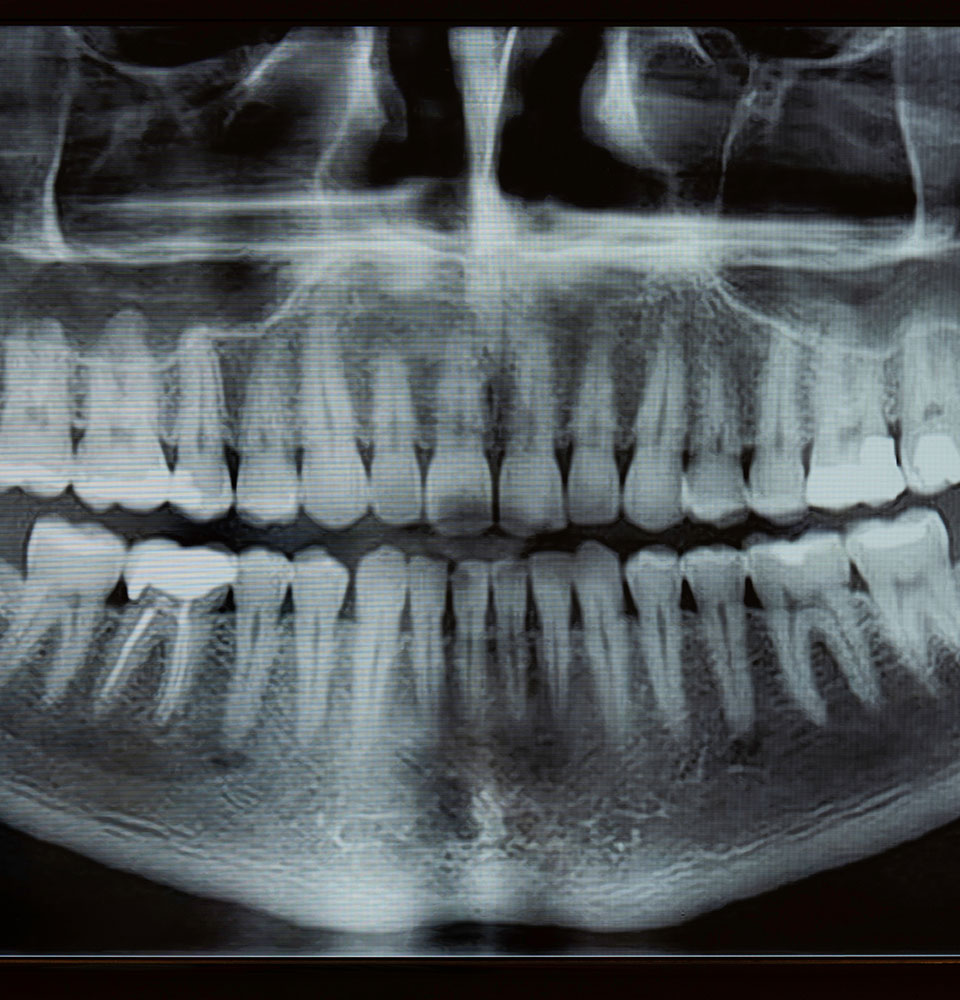

At HAR Dental Group, your treatment is personalized, precise, and streamlined. Here’s how it works: 1. Consultation & 3D Imaging Your visit includes: Full exam 3D CBCT scan Smile evaluation Bone and gum analysis Medical history review This allows Dr. Harmouche to determine your exact needs and create a customized plan. 2. Digital Smile Design […]